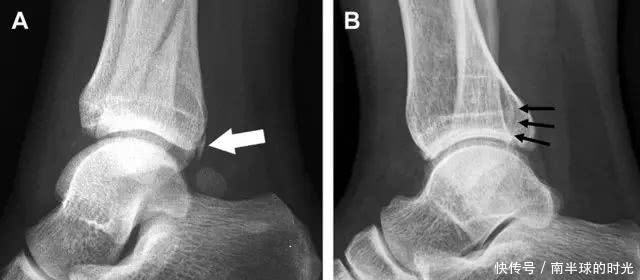

跟骨前突骨折

呈 Y 形的分歧韧带附着于跟骨前突上,是维持踝关节跖屈和背屈稳定性的重要结构。跟骨前突骨折常发生于足跖屈内旋、分歧韧带被牵拉时,或者足背屈外旋、骰骨和距骨挤压前突时。而这些骨折在初次 X 线检查时常常被漏诊掉。踝部侧位片诊断这些骨折最佳,准确诊断的关键点在于,必须仔细查看是否存在骨皮质中断(图 6)。如果侧位片可疑,建议加做斜位片协助诊断。

图 6 跟骨前突骨折。A 侧位片示跟骨前突骨折(箭头),与舟骨的重叠使骨折显示模糊;B 另一位患者的侧位片示内翻损伤所致的骨折(箭头),这种损伤机制引起小块的骨折